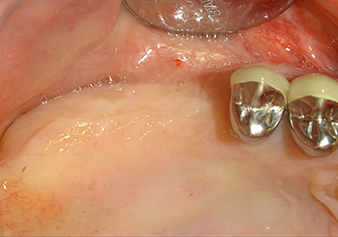

Following atraumatic preparation of the mucoperiosteal flap, the implant position was marked with the I1 instrument and the site prepared – until initial resistance was felt. Piezosurgical instruments were used in an up and down movement without any pressure being exerted. The piezoelectric vibration produced the desired and efficient cavitation.

The I2A instrument (diameter 2.0 mm) was then used to perforate the sinus floor intermittently and on the smallest scale possible. This special piezosurgical method ensures that the Schneiderian membrane is not damaged. When the Z25P was used, the membrane was already lifted slightly by the coolant supplied via the instrument tip (Fig. 3). The coolant quantity was just 50% in order to avoid high pressure in the implant bed.